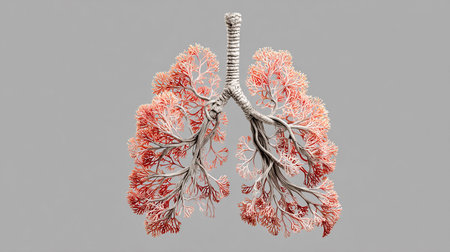

?reative magical illustration with Tree branches like the lungs. World No Tobacco Day and Great American Smokeout. Stop smoking and get healthy respiratory organs concept

A detailed, artistic representation of a diseased lung, featuring a network of red and white structures. The image shows the internal anatomy, highlighting the affected areas.

This 3D image of human lungs provides a stunning view that intricately showcases the anatomy and functionality of our respiratory system. With an X-ray style inspired by science and medicine, the visualization emphasizes the importance of understanding lung health and the mechanisms that sustain our breathing and overall well-being. This captivating representation is essential for medical education and research.